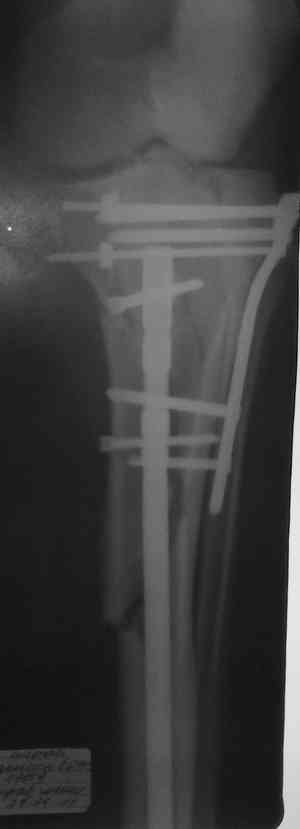

[Ortho] Комбинированный синтез перелома голени

Имя     : 293.jpg